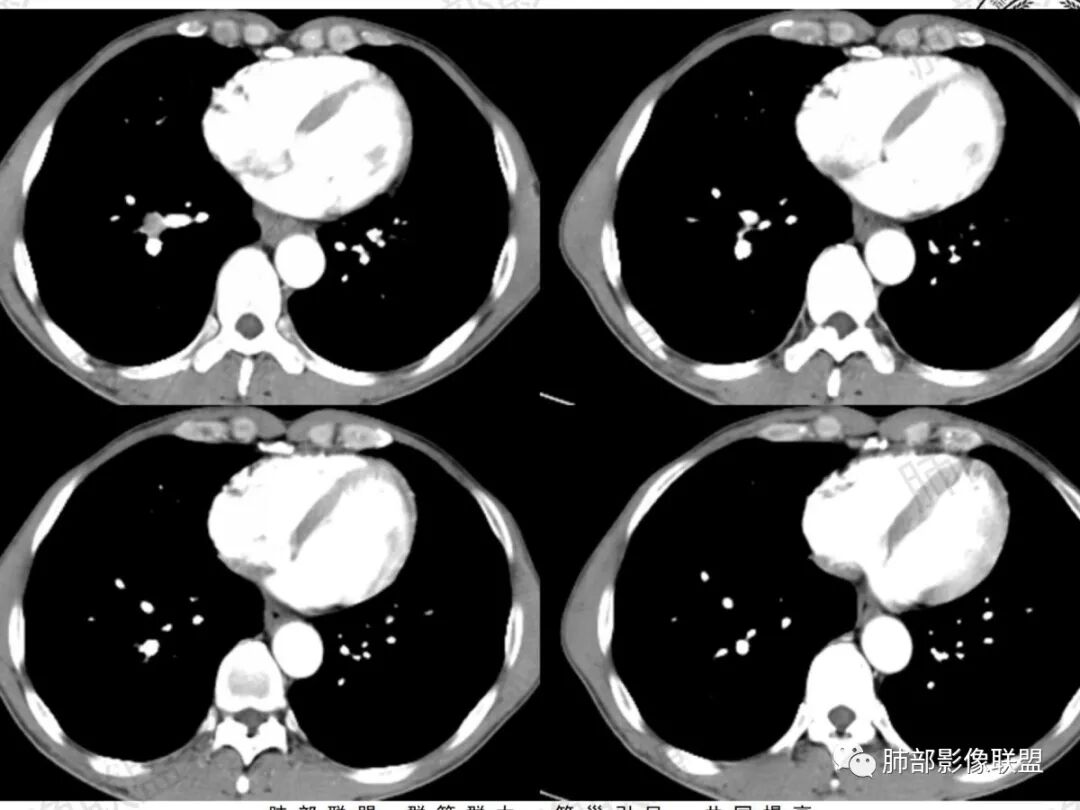

两肺门及纵隔淋巴结增大,部分融合,不均匀强化,可见坏死,两肺多发微结节,腹腔环形强化淋巴结,一月前胸CT未提示肿大淋巴结,考虑恶性,转移瘤?小细胞癌?鉴别结节病

中年男性,干咳半年。双侧肺门纵隔对称性淋巴结肿大,大部分肿大的淋巴结与周围血管之间的脂肪间隙消失,部分有融合坏死,无钙化;肺内多发小结节,右侧叶裂多发结节,腹膜后淋巴结肿大并坏死。考虑纵隔及肺门肿大淋巴结考虑为转移可能性大,鉴别结节病(淋巴多不融合、可见钙化)、结核(可融合、环形薄壁强化)。

双肺门及纵隔对称性淋巴结肿大,有融合坏死,肺内多发粟粒结节,叶间裂也有,右肺上叶前段亚段支气管狭窄,腔内密度增高;腹膜后淋巴结肿大坏死,老年男性,4月外院没提淋巴结,考虑结核,鉴别淋巴瘤,转移瘤,结节病,鳞癌

这淋巴结很符合结核的干酪坏死

该病例增大淋巴结与周围结构的毗邻关系是有特征性的,结合强化特点,可简单排除结核、淋巴瘤和小细胞癌

结节病的淋巴结与毗邻结构边界常相对清晰,易产生质感较硬的接触和挤压,较之淋巴瘤明显的多。淋巴瘤是“糊”,虽有挤压,但有更多糊的成分,相对质感软一点。结核最常见的淋巴结是2、4、7、10等淋巴结增大,质感软,与毗邻结构糊的意向更明显。小细胞癌也是糊,还有包绕

结节病可以有坏死,但几率和程度常较小

结节病的肺门及纵隔淋巴结增大也较有特点,较少融合,较坚硬密实,密度偏高,可钙化。偶或可以观察到低密度坏死,但较少且轻微。

4.肺门淋巴结结核:多以单侧为主,内常见钙化,淋巴结可融合,易坏死且范围较大,增强扫描典型的环形强化。